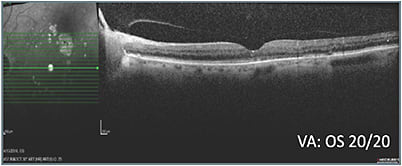

When this 69-year-old male with a history of PDR, DME, and multiple treatments, including laser, was referred from another practice, it was noted that he had poor response to prior treatment. The patient was pseudophakic and did not have glaucoma. His visual acuity was 20/50 OD and 20/30 OS. OCT indicated the need for treatment (A).